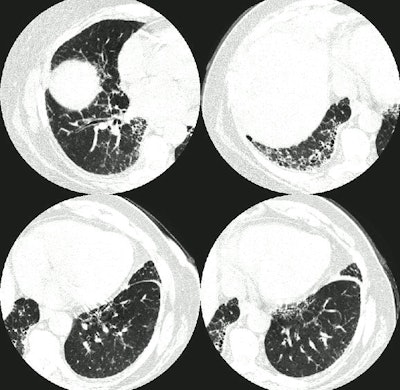

The CT scan demonstrates interlobular septal thickening and the presence of "honeycombing" within the lung bases- most pronounced in the right lower lung.